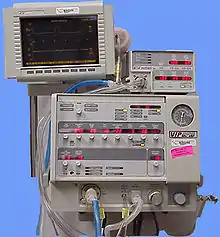

Ventilation

Positive pressure ventilation, in which air is forced into the lungs, is needed when oxygenation is significantly impaired. Noninvasive positive pressure ventilation including continuous positive airway pressure (CPAP) and bi-level positive airway pressure (BiPAP), may be used to improve oxygenation and treat atelectasis: air is blown into the airways at a prescribed pressure via a face mask.[39] Noninvasive ventilation has advantages over invasive methods because it does not carry the risk of infection that intubation does, and it allows normal coughing, swallowing, and speech.[39] However, the technique may cause complications; it may force air into the stomach or cause aspiration of stomach contents, especially when level of consciousness is decreased.[4]

People with signs of inadequate respiration or oxygenation may need to be intubated[7] and mechanically ventilated.[12] Mechanical ventilation aims to reduce pulmonary edema and increase oxygenation.[27] Ventilation can reopen collapsed alveoli, but it is harmful for them to be repeatedly opened, and positive pressure ventilation can also damage the lung by overinflating it.[57] Intubation is normally reserved for when respiratory problems occur,[7] but most significant contusions do require intubation, and it may be done early in anticipation of this need.[4] People with pulmonary contusion who are especially likely to need ventilation include those with prior severe lung disease or kidney problems; the elderly; those with a lowered level of consciousness; those with low blood oxygen or high carbon dioxide levels; and those who will undergo operations with anesthesia.[41] Larger contusions have been correlated with a need for ventilation for longer periods of time.[15]

Pulmonary contusion or its complications such as acute respiratory distress syndrome may cause lungs to lose compliance (stiffen), so higher pressures may be needed to give normal amounts of air[4] and oxygenate the blood adequately.[33] Positive end-expiratory pressure (PEEP), which delivers air at a given pressure at the end of the expiratory cycle, can reduce edema and keep alveoli from collapsing.[13] PEEP is considered necessary with mechanical ventilation; however, if the pressure is too great it can expand the size of the contusion[17] and injure the lung.[39] When the compliance of the injured lung differs significantly from that of the uninjured one, the lungs can be ventilated independently with two ventilators in order to deliver air at different pressures; this helps avoid injury from overinflation while providing adequate ventilation.[58]